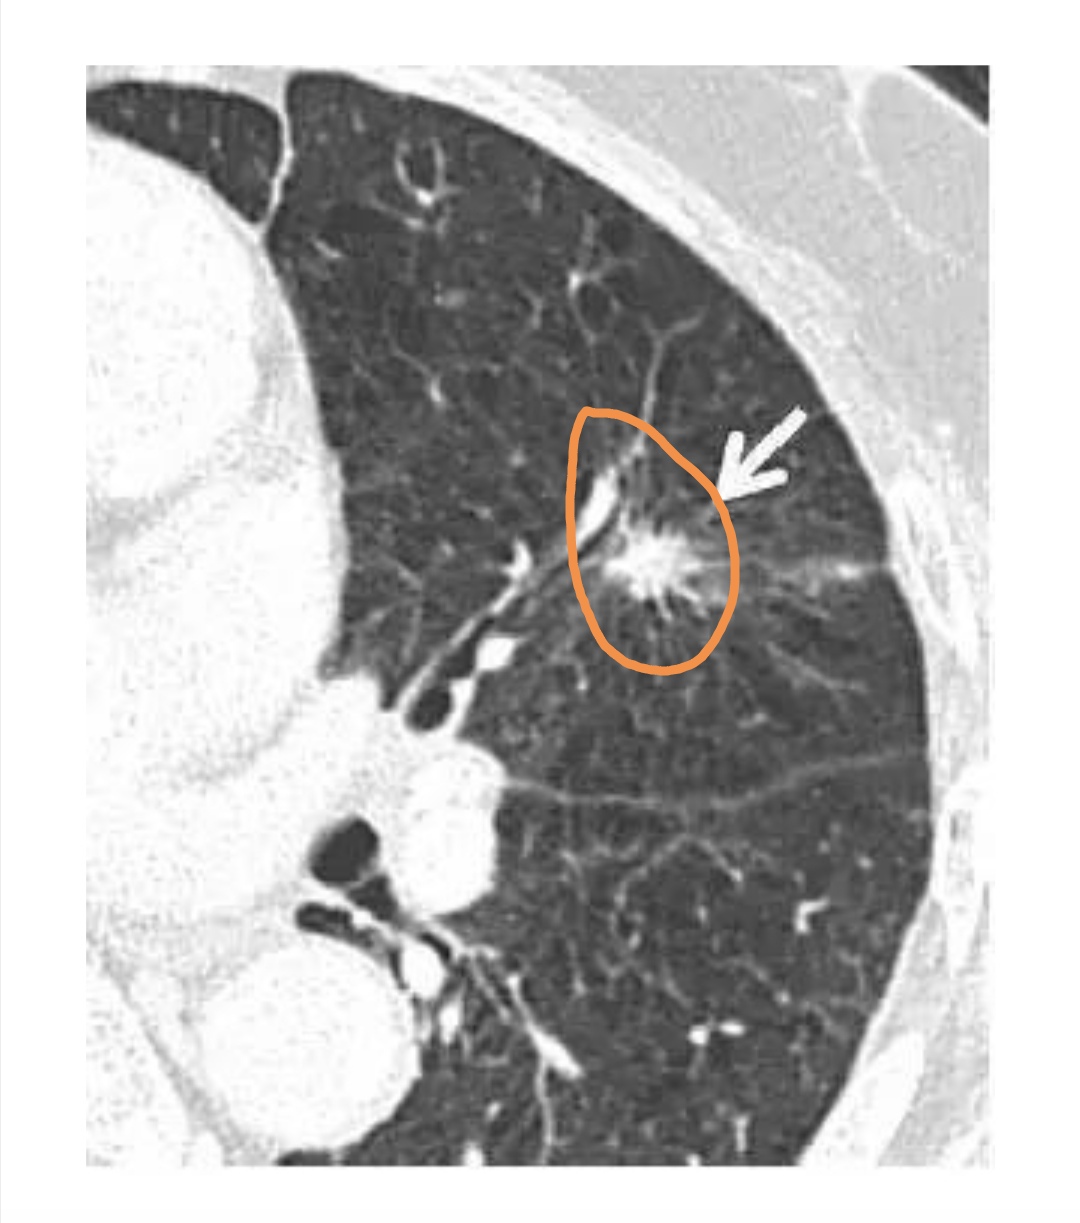

实性毛刺状结节,恶性